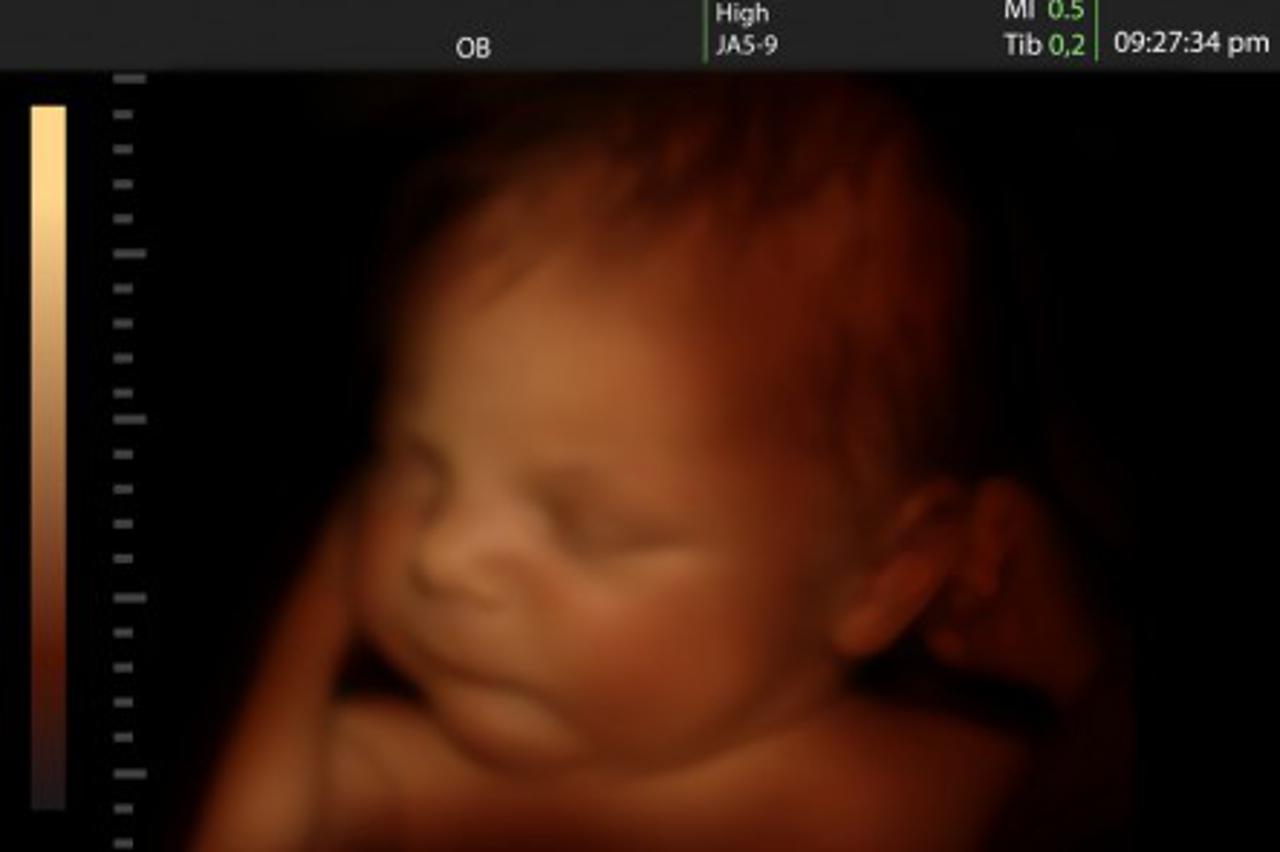

'Na slici s ultrazvuka beba mi poručuje da je sve u redu'

Ellini pratitelji primijetili su kako bebino čelo i nos neodoljivo podsjećaju na Charlesov.